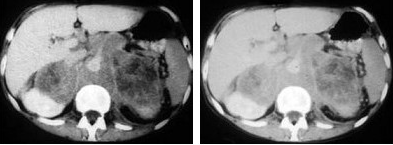

男,76岁,全身浅表淋巴结肿大,请结合下列图片作出诊断( )

A:肾上腺腺瘤

B:肾上腺癌

C:肾上腺嗜铬细胞瘤

D:肾上腺转移瘤

E:肾上腺淋巴瘤